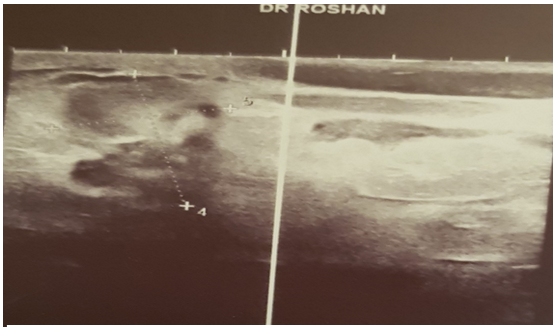

With S&S and XR of knees and ankles of Patient show arthritis of the right and left ankle and both knee with swelling and edema. Vital examination for fever was 38 degree in centigrade. Lab date in Acute phase reactants were elevated [erythrocyte sedimentation rate: 95 mm/hour (normal, 0-20)], [C-reactive protein levels: 119 mg/L (normal, 0-3)]. Leukocyte count was (12800/L). Ultrasound examination of breast excluded breast abscess, but showed a 4 cm mass with edema of skin (Figure D).

Figure D: Ultrasound examination of breast excluded breast abscess, but showed a 4 cm mass with edema of skin on the left breast.